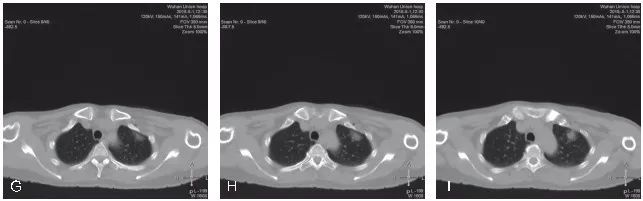

不良事件的发生率在可接受范围内。气胸是经胸廓细针穿刺活检最常见的并发症,发生率为16.0%~51.8%。在341位患者中,只有7位患者需要留置胸腔引流管。咯血发生率为8%~23%,没有患者需要治疗。从穿刺技术层面上来看,GGO的穿刺活检与普通肺结节的穿刺活检基本类似,同样需要注意避免引起气胸或出血的危险因素,从总体诊断效能及并发症发生情况来看,与普通肺结节大体一致。但也有部分研究者认为,GGO本身为经皮肺穿刺活检发生出血的一个危险因素,分析其可能的原因主要是GGO的体积通常较小,在使用全自动活检枪进行切割式活检时会损伤到更多的肺策划及肺内血管,导致较为明显的肺内出血。我院完成的GGO穿刺活检同样表现为较为明显和广泛的肺内出血征象(图5-2~图5-4)。这一点在小结节的穿刺活检中同样经常出现。因此,我们要求对于小结节/GGO的穿刺活检,务求“一击必中”。因活检取材易出现较明显的肺内出血征象,如取材不满意,即使再次进行CT扫描,亦可能无法为我们提供有效的影像引导,导致最终无法进行有效的调整,导致活检取材失败。

图5-2 A~C. 显示患者右肺下叶后基底段mGGO,选取俯卧位进行穿刺活检;D~F. 显示穿刺活检的实时CT影像,选取最短的穿刺路径,并尽量使同轴穿刺针与较粗大的肺内血管平行。图中显示同轴穿刺针到达预设位置,并未紧邻靶结节表面,为活检预留好空间,以免损伤该结节远端的肺内血管;G~I. 显示完成活检后,拔除同轴穿刺针。再次进行CT扫描,见靶结节活检区域明显的肺内渗出性改变,提示较严重的肺内出血。病理结果示:(右肺)浸润性腺癌